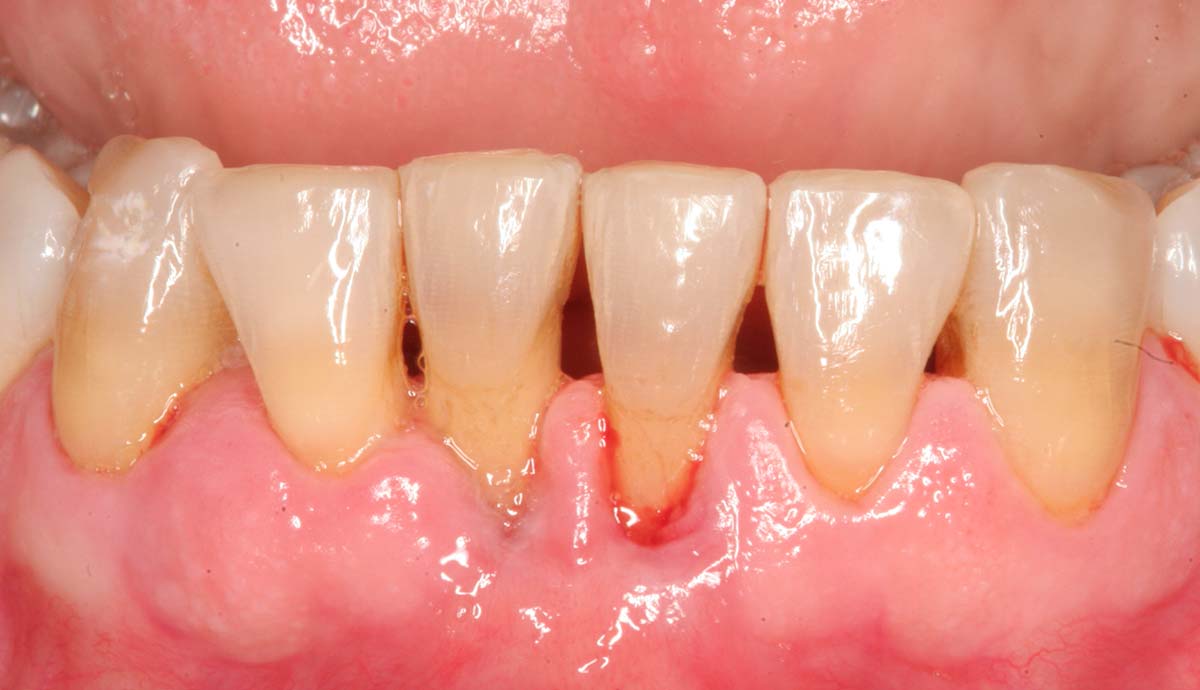

- Пародонтит — воспалительное поражение тканей, окружающих зуб. При этом заболевании образуются зубодесневые карманы и наблюдается опущение десны. Из-за этого зубы становятся более чувствительными и болезненно реагируют на внешние раздражители. Другими признаками пародонтита являются зуд десен, кровоточивость и неприятный запах изо рта. Особенно сильно зуб болит при нажатии и пережевывании пищи, иногда он расшатывается. Запущенную форму болезни лечат хирургическим способом.

- Гингивит — воспалительное заболевание десен, которое проявляется болью в одном или нескольких зубах. Если в десневых карманах начинается нагноение, появляется неприятный запах изо рта, зуб начинает шататься, а десны кровоточат. Болевые ощущения возникают внезапно, например, во время пережевывания пищи, особенно горячей, холодной и кислой.